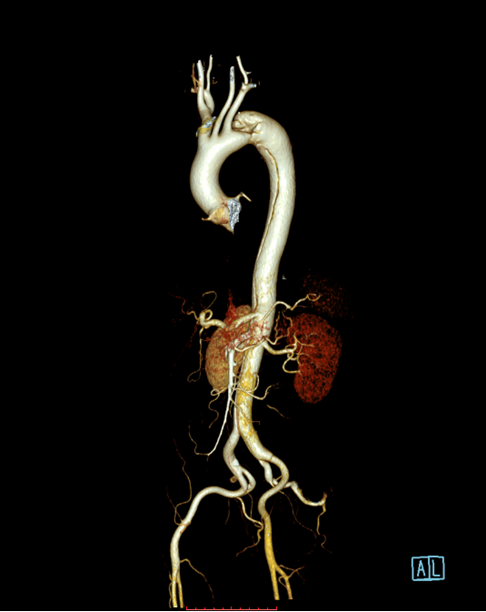

患者以“突发胸背部疼痛1月余”为主诉急诊入住中南大学湘雅二医院血管外科,入院后经过CTA确诊为“主动脉夹层”,夹层第一破口紧邻左锁骨下动脉,且左锁骨下动脉起始部呈局限性夹层样改变,胸主动脉真腔全程受压,病情十分危重,患者疼痛难忍!

经过仔细测量及讨论,根据患者夹层真腔受压严重、近端锚定区不足,左锁骨下动脉累及到血管根部以及病情比较危重的特点,舒畅教授决定使用目前已开展的临床试验研究项目(PATENCY study/NCT03767777)“先健新型主动脉弓烟囱支架”,该研究是先健科技公司与舒畅教授合作研发的新型主动脉弓烟囱支架,对于累及弓上分支的主动脉夹层、且病情比较紧急的患者具有明显的优势!

先健科技的新型主动脉弓烟囱支架适用于累及主动脉弓的胸主动脉夹层,产品由Ankura™ Pro主动脉主体覆膜支架系统和Longuette™主动脉分支覆膜支架系统组成。

术中通过DSA造影显示:主动脉夹层破口位于左锁骨下动脉近端,真腔压闭!舒畅教授为患者完美的实施TEVAR+左锁骨下动脉裙边烟囱支架置入术,手术过程非常顺利,胸主动脉支架释放良好,患者的主动脉夹层破口封闭良好,真腔打开良好,左锁骨下动脉释放的裙边支架血流通畅,没有内漏发生。